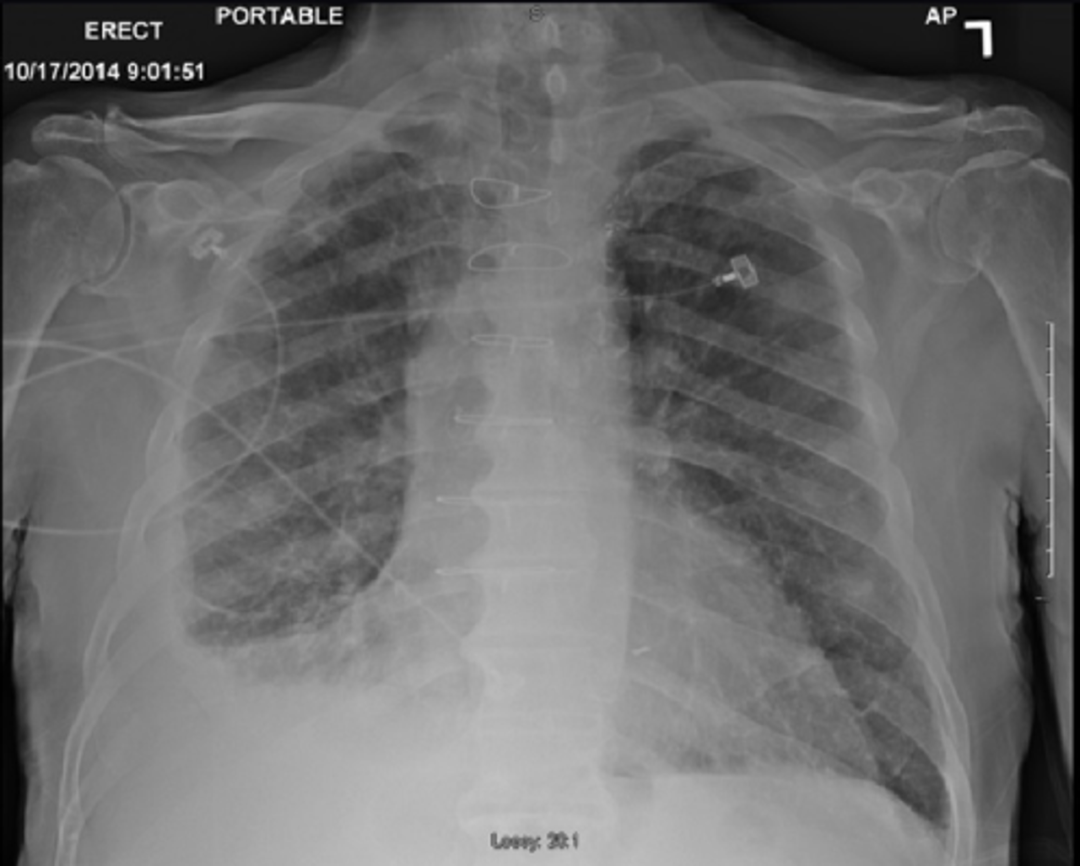

由塵肺引起的纖維胸和胸腔積液 圖源:Salih M, Aljarod T, Ayan M, Jeffrey M, Shah BH